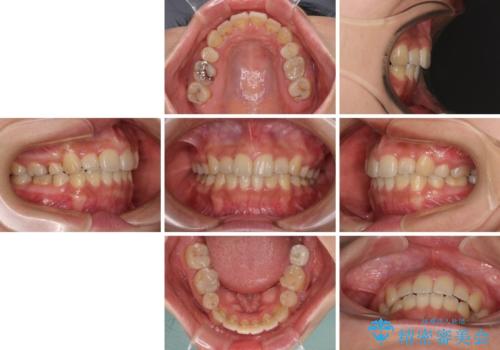

デコボコと膨らんだ口元 ハーフリンガルによる抜歯矯正とインプラント補綴治療

また、左下の奥歯は抜歯が必要な歯であったため、矯正治療中の良いタイミングで抜歯とインプラント埋入を行い、矯正治療後にオールセラミッククラウンで補綴治療を行うこととしました。

デコボコの解消までは非常にスムーズでしたが、咬合力が強いためか、スペースを閉じるまでに長い期間を要しました。

矯正治療途中にインプラント埋入と仮歯の装着を行ったことで、しっかりとした奥歯の咬み合わせで終了させることができました。